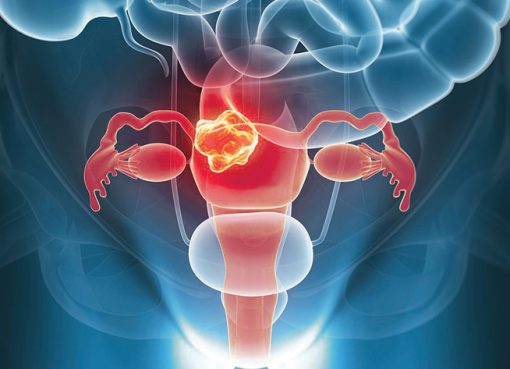

Women’s Health A to Z

March 26, 20210454

#CareForHerHeart by helping her manage her stress better